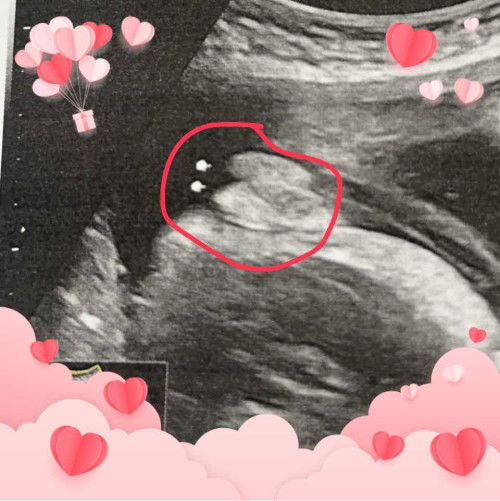

แบบนี้เพศหญิงหรือชายค่ะ แอบกังวล คนทักกับผลซาวไม่เหมือนกัน😂

#คุณแม่ๆช่วยแนะนำหน่อยค่ะ